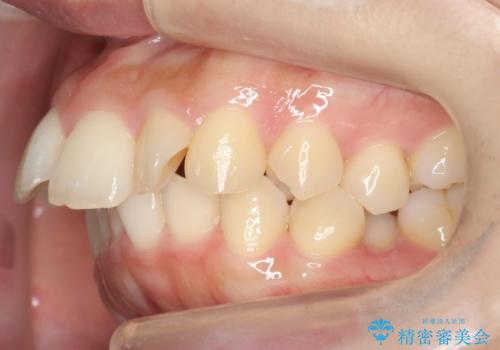

- 出っ歯を主訴に来院。

上下のかみ合わせが1本分左右ともずれていました。

下顎がとても小さく後方位であるため、オトガイの閉口時のシワは完全になくすことは難しかったですが、前歯も大きく下がり満足していただきました。

矯正治療は審美的な側面を持っておりますが、小さすぎる下の顎に口元を無理やりあわせるのも、歯の移動量が大きすぎて適切な治療とは言えないと思います。健康を損なう美容整形とは違うからです。前歯については、適度に下げる量をコントロールすることも大事です。